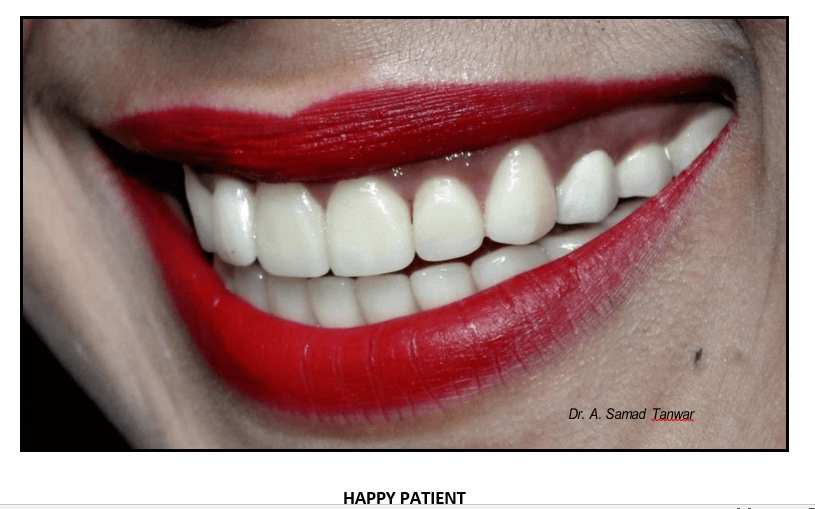

Lithium disilicate glass ceramic was fabricated for maxillary and mandibular Lithium disilicate (Emax) is an aesthetic, high strength material that can be conventionally cemented or adhesively bond.

Lithium disilicate is among the best known glass

Calibra esthetic resin cement was used for the bonding of laminates.

Occlusal view of the restorations In-situ

Restoration of aesthetic and function by using blend of conventional and minimally invasive